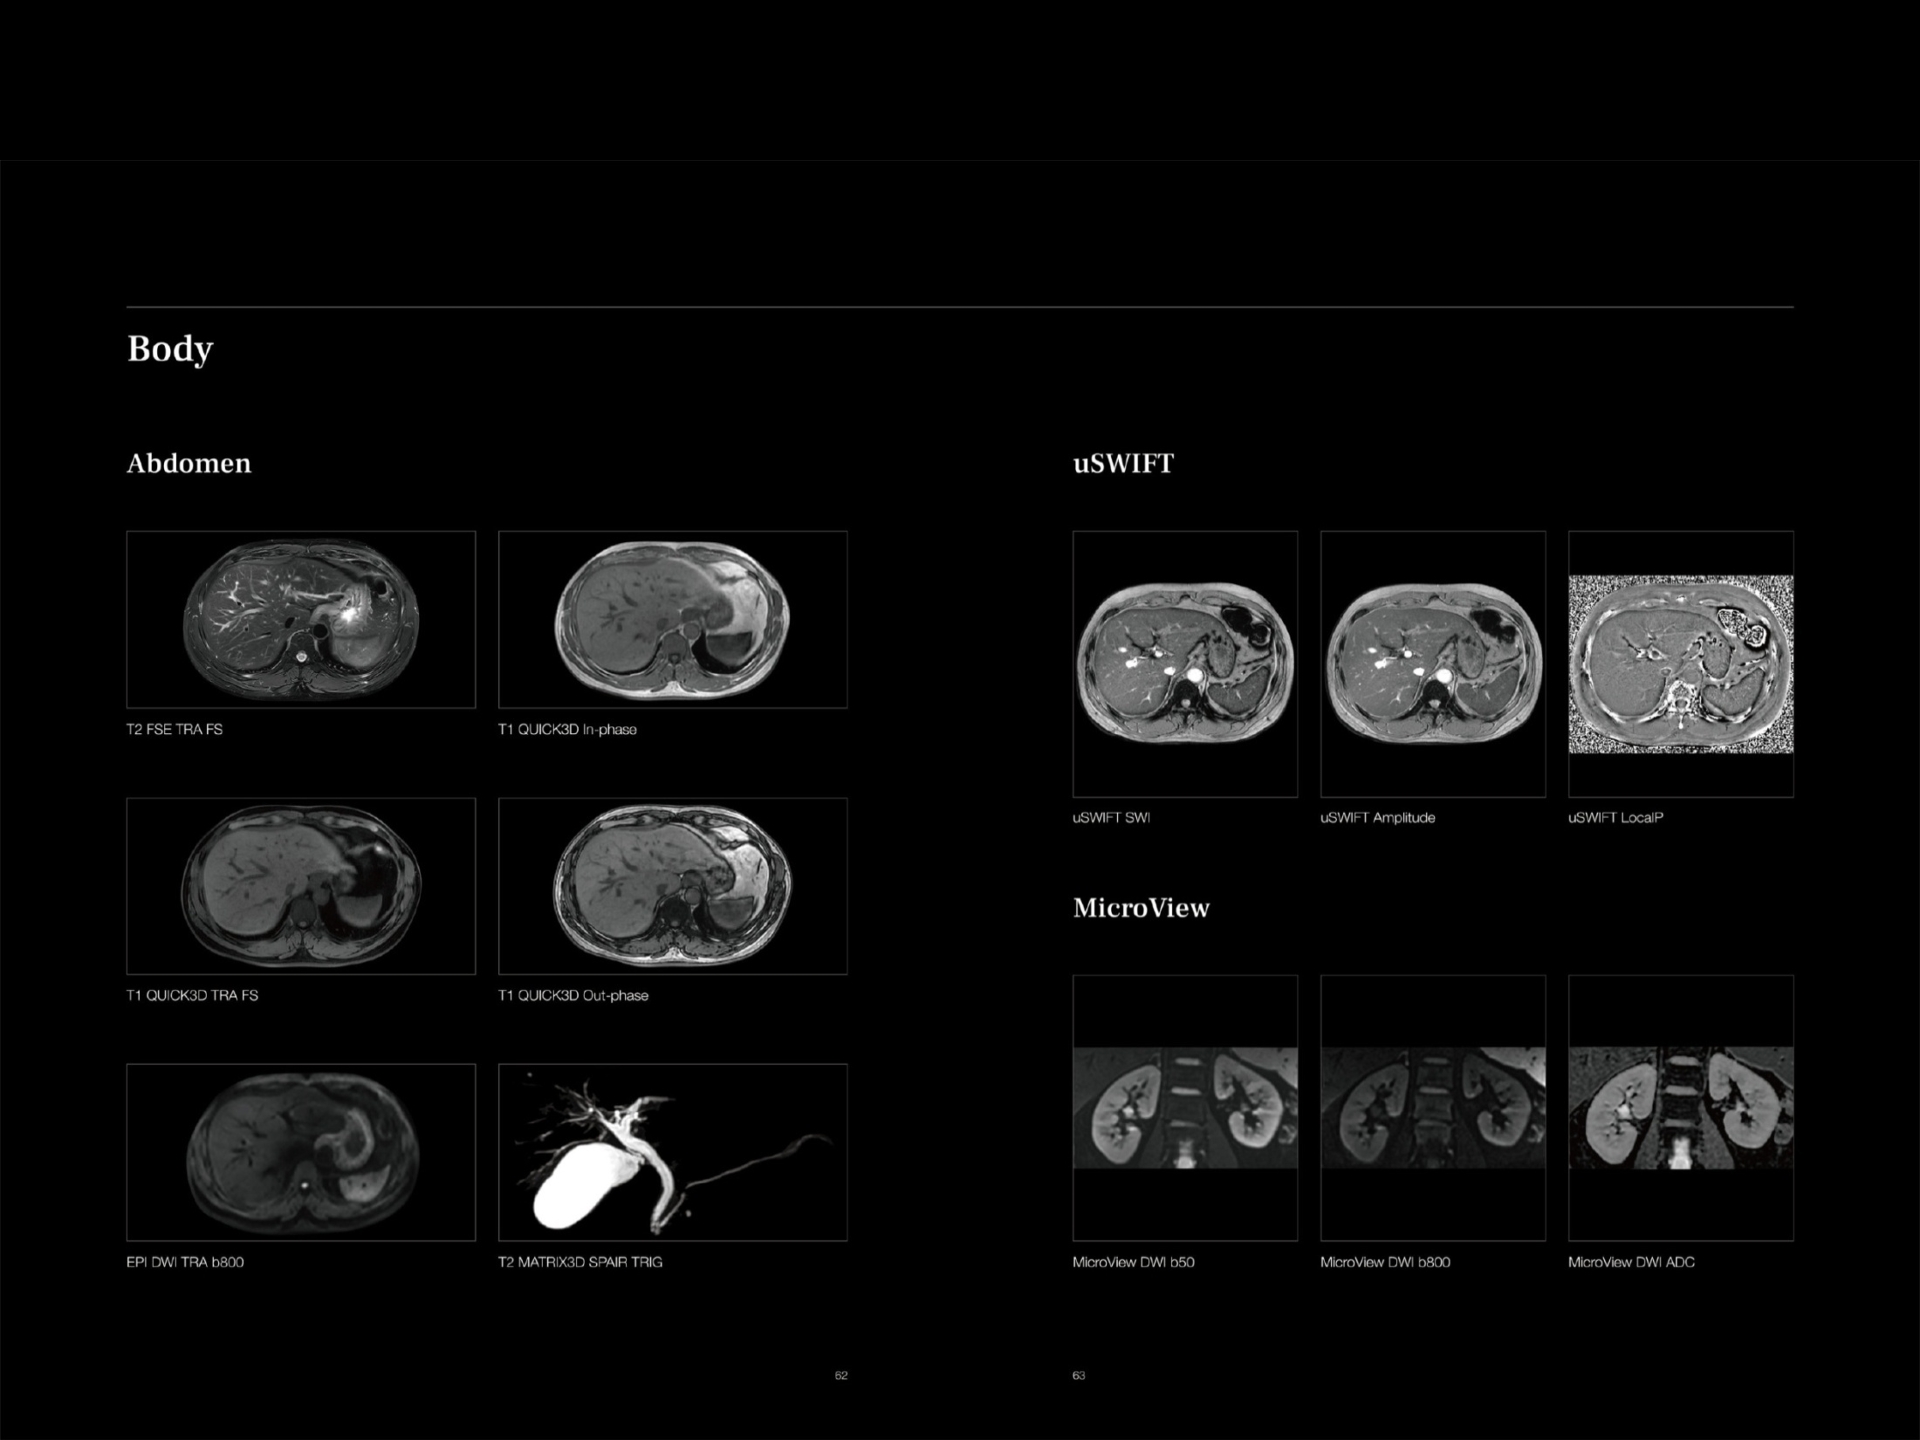

Machine has 24 dedicated Superflex body coils designed for comfort and coverage for whole body MRI and special infant coil.